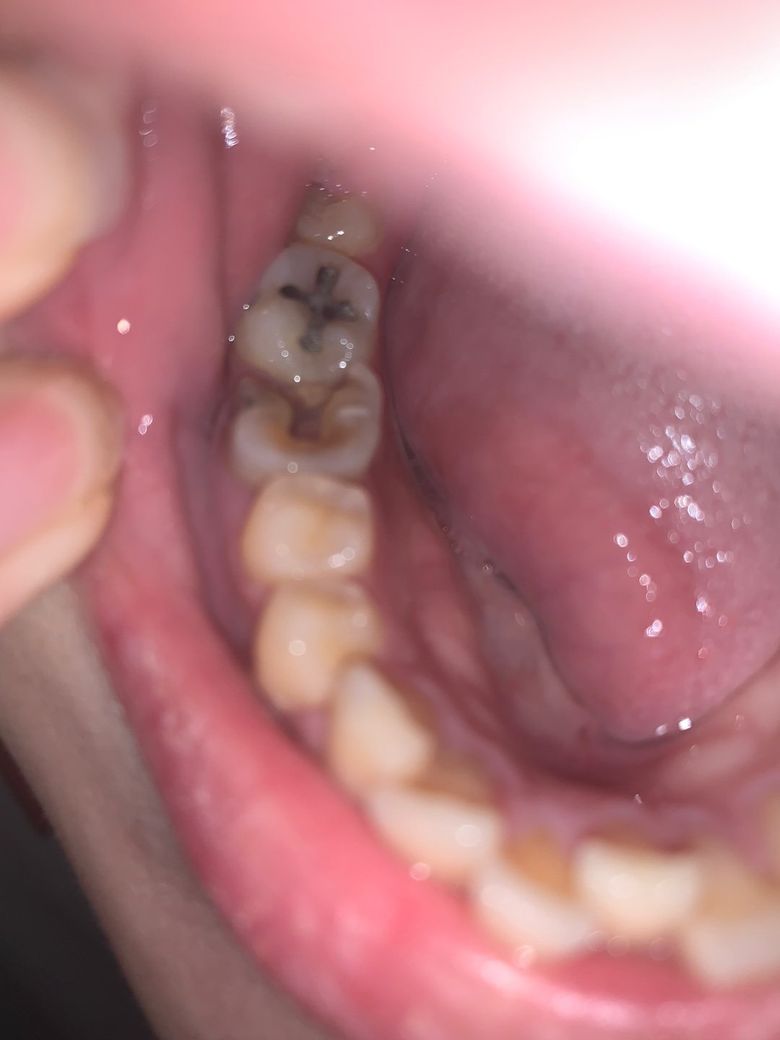

어제 10일 아침에 일어나니 볼안쪽이 심하게 부어있고 거울을 봐도 볼걸이 마냥 오른쪽 볼이 살짝 부어있는게 티가 날 정도였어요.. 그리고 침삼킬때 진저리 칠정도로 목이 아파요.. 목도 전체적으로 아픈게 아니라 오른쪽 부근만 아파요.. 따갑다는 표현이 맞을지.. 상처난데에 물 닿으면 아픈 느낌 불타는 느낌?? 무튼 침을 삼킬때 목이 너무 아파서 그냥 모았다가 한번에 삼키거나 뱉어버려요.. 어제 일요일이라 병원도 다 닫아서 탁센 먹었는데(아침에 한알 저녁에 한알 먹고 잠) 저녁쯤 되니 붓기는 좀 가라앉았어요... 근데 탁센 먹어도 침삼킬 때 목톡증은 통증 정도만 좀 낮아졌지 여전히 아팠어요..ㅠ 지금도 입술 막 움직여보면 왼쪽은 멀쩡한테 오른쪽이 많이 부어서 어금니들에 부벼대는 느낌.. 그래서 이게 이비인후과로 가야하는지 치과로 가야하는지 모르겠네요.. 사진상 보이는 어금니 깨져있는 듯한 치아는 사실 신경치료 다 끝나고 크라운으로 씌웠어야 했는데 돈이 부족하고 비싸서.. 장기간 신경치료만 마친 채 방치된 상태에요.. 그래도 신경치료를 해놔서 그런지 별다른 통증 없이 지내왔는데 갑자기 저 치아 잇몸이 하얗게 부어있고 볼안쪽도 심하게 붓고 ... 혹여나 사랑니때문인가 싶기도 하고.. 근데 왜 목은 타들어갈듯 아픈건지.. 자세한 답변 좀 부탁드려요..ㅠ 제가 월급이 한 3일 이내로 나올 듯 한데.. 여유 돈이 없어.. 몇 일이라도 이 통증을 없앨 수 있는 방법이 있다면 이것도 좀 알려주세요.. 탁센은 목통증에 잘 안드는 듯 해서요..ㅠ

사랑니로 인한 지치주위염 혹은 신경치료 중단 후 방치된 치아의 염증 재발 소견으로 보입니다.

사진으로만 봤을 경우에도 우측 하악 1대구치의 치질의 손상이 많이 되어 있는 것으로 보입니다.

신경치료를 마무리 했어도 크라운등의 보철치료를 하지 않으면 메꾼재료가 떨어지거나 안쪽으로 감염이 진행되어 치근단 염증을유발할수 있어요.